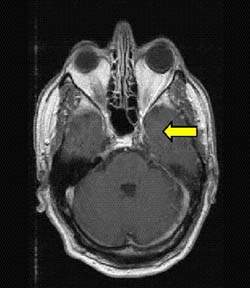

До терапии 3 месяца спустя

после ионной терапии